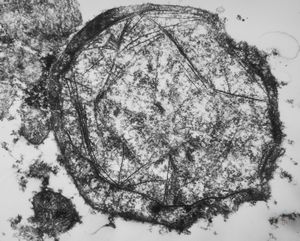

M,71y. | amyloid - glandula vesiculosa

M,56y. | amyloid - tendon